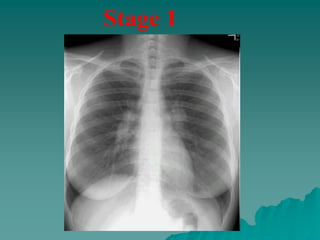

 Chest radiographs in patients with sarcoidosis have been

classified into four stages:

– stage 1, bilateral hilar lymphadenopathy without infiltration.

– stage 2, bilateral hilar lymphadenopathy with infiltration.

– stage 3, infiltration alone.

– stage 4, fibrotic bands, bullae, hilar retraction, bronchiectasis,

and diaphragmatic tenting.

 These so-called stages represent radiographic patterns and do

not indicate disease chronicity or correlate with changes in

pulmonary function.

Stage 1